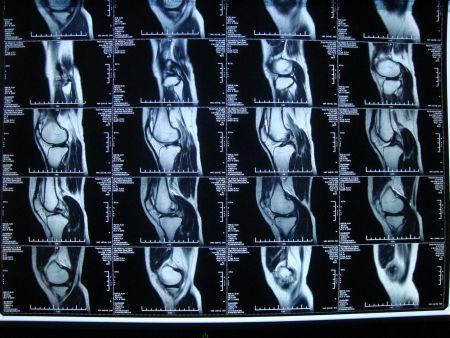

核磁共振會產生輻射?造價上千萬的醫療設備,我國能自主研制嗎?

核磁共振是當代生活無法規避的一個課題。經由核磁共振儀這項科學化儀器,人類的身體內部結構迅速神奇的透明化,內部器官的成像高效透露身體的早期病變,醫者對癥下藥,及時維護病人們的生命健康。

但在核磁共振儀進入中國醫學的這些年,看到以"核"開頭的冷冰冰字眼,我們常常會擔憂科學儀器對身體造成或多或少的輻射,對身體產生不可逆的傷害,不經意之間從心底產生排斥。然而,核磁共振儀真的會產生核輻射嗎?他具體又能夠救治哪方面的疾病?在中國的醫療市場上,核磁共振儀的價格折射出怎樣的科技維度?今天的中國,是否可以自主獨立地開辟核磁共振成像技術的新天地?

隨著MRI技術的日趨成熟,醫學的科學性也隨之提升,從深處溯源,核磁共振技術就是利用水體中氫原子的信號反應來確定水分子在生物體內的分布結構,從而探測人體生理結構的完整性。

人類身體的三分之二由水構成,水又由氫原子和氧原子構成。當我們的肉身暴露在磁核共振儀下,就會引起氫原子的共振反應,通過這樣的聚合磁場,人體內部的水分子就會呈現出一定的梯度,從而形成人體內部結構的影像。

核磁共振儀需要磁鐵來產生磁場,目前的技術裝置主要分為超導、永久、電磁等三類磁體,磁場強度越高,氫原子的激發頻率就越高,這意味著成像的分辨率和靈敏度會提升多個進階。我們用肉眼可見到的圖譜成像就更能一目了然。

T是核磁共振磁場調度的單位,所承載的字數越大,相對應的效能更好,據了解,1.5T大約處于500-1100萬的價格區間,而3.0T的造價應該在1200-2400萬之間,一臺上好的核磁共振儀需要超過千萬的成本報價,這樣昂貴的數字背后,其實還剔除了成產過程中的人力成本、場地成本,還有一年四季維系裝置運行的電費。

能夠產生高度穩定和均勻的強磁場是技術的核心所在,今天的中國醫院都配備了質量客觀的核磁共振,也有醫院進口了1.5T類型的核磁共振,但更高強度的3.0T卻幾乎處于空白狀態。把視野發散到世界全球,能夠獨立生產核磁共振儀的國家寥寥無幾。